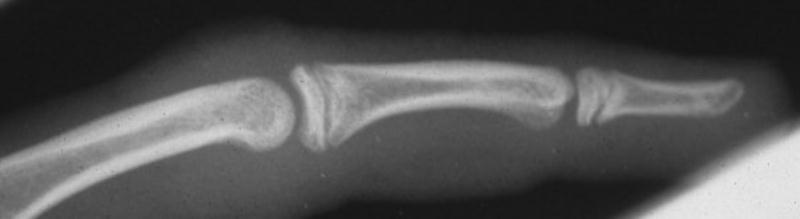

Case 1. 14 year old boy with radial prominence and ulnar deviation of the middle finger proximal interphalangeal joint. Painless, no history of trauma.

Radiographs showing well circumscribed calcification at the  proximal phalanx collateral ligament origin, 10 degrees of lateral angulation.